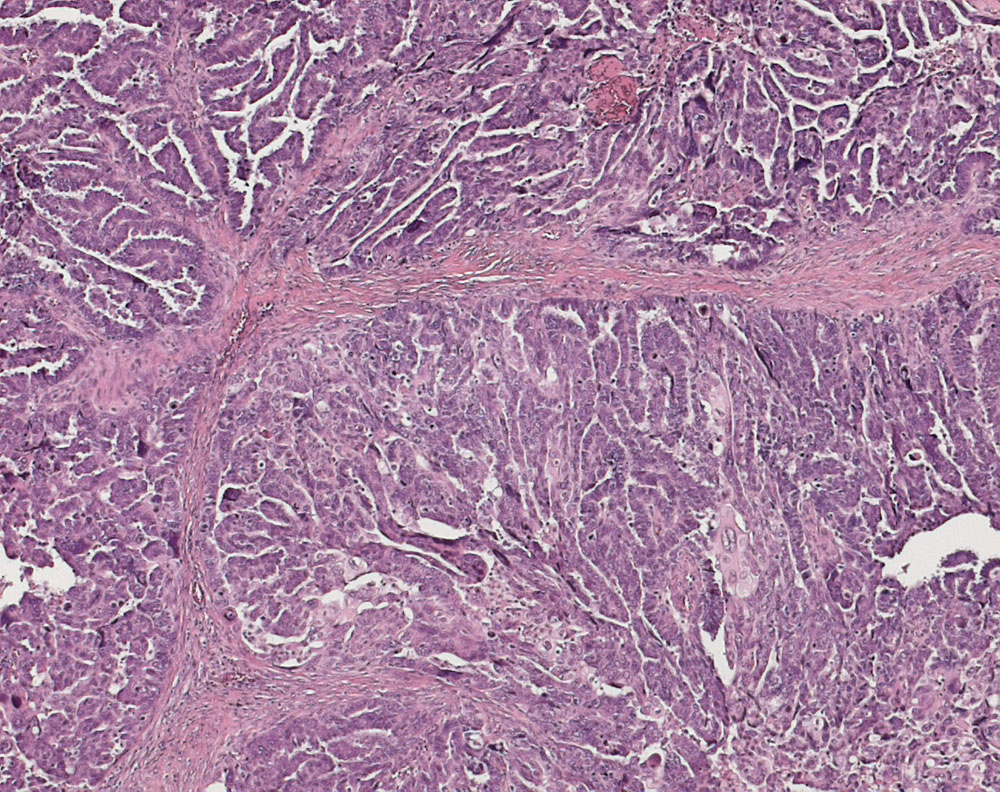

PathoPic ID 10936 - seröses Ovarialkarzinom high grade

seröses Ovarialkarzinom high grade

Papillen und Drüsen mit schlitzförmigen Lumina.

Verdacht auf Ovarialkarzinom (CA125 > 2000u/l). CT: Vergrösserte Ovarian beidseits. Maligner Pleuraerguss Adenokarzinom.

Histologie

25